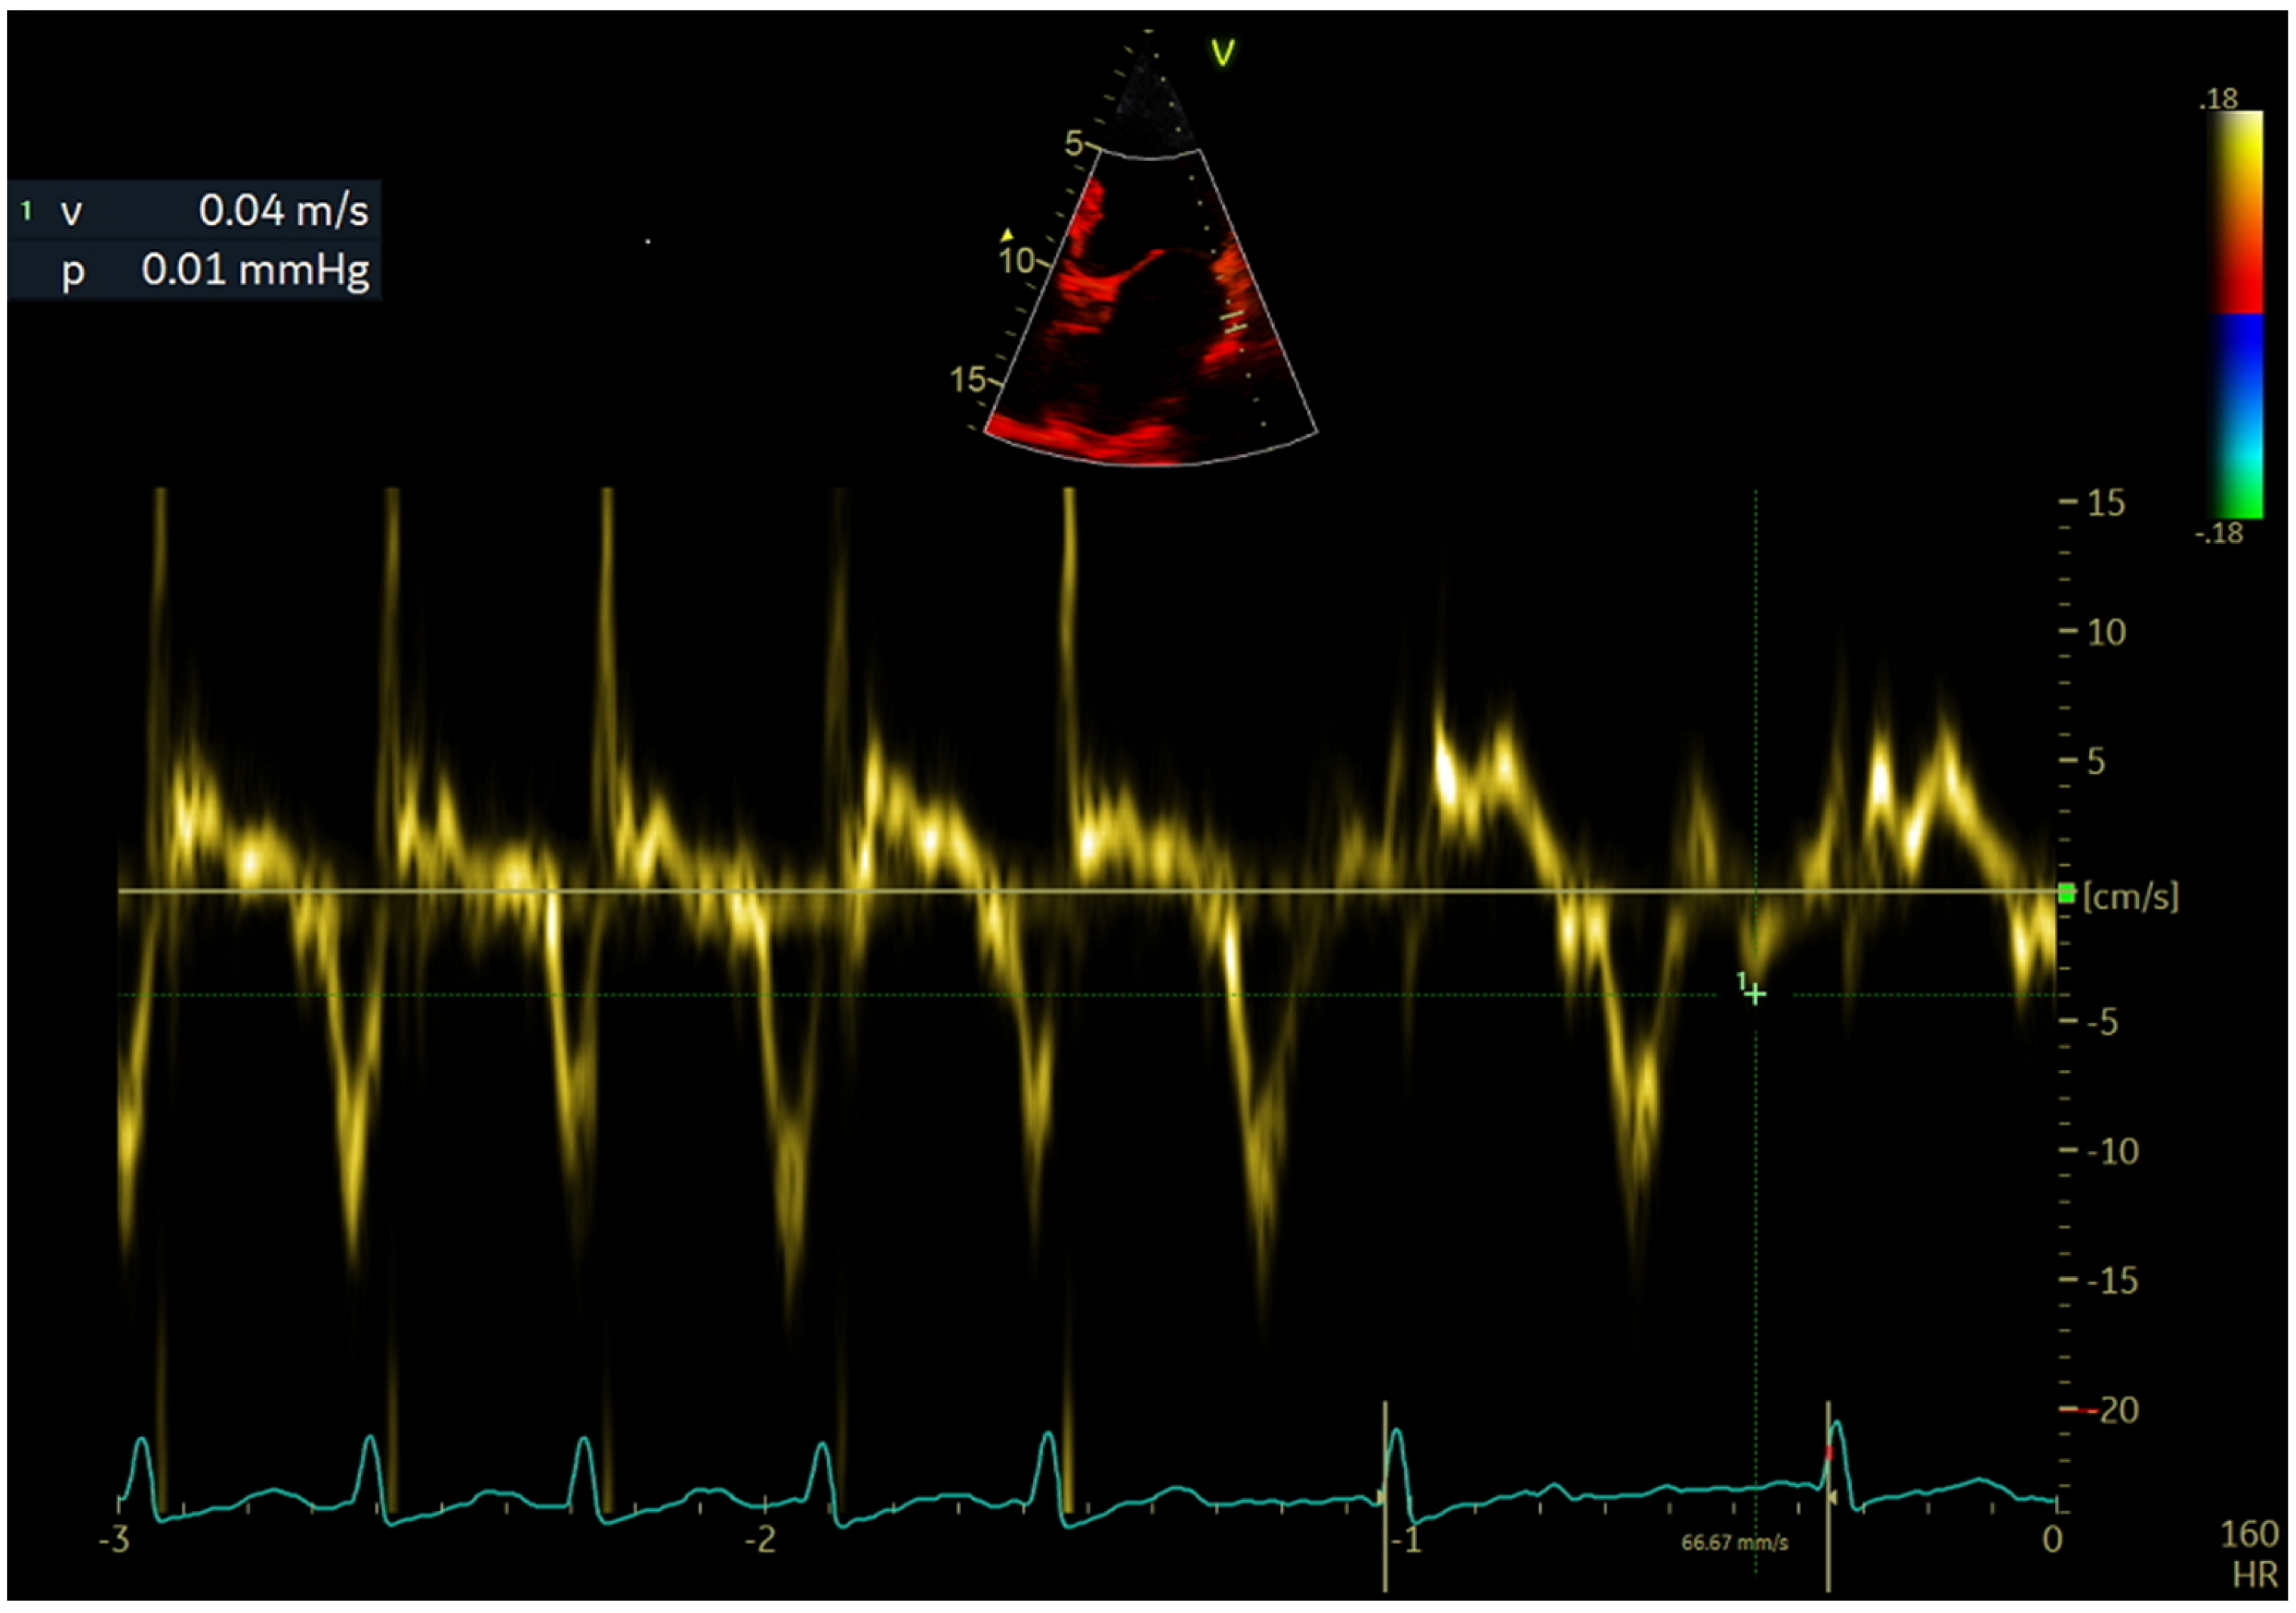

2.4. Echocardiographic Evaluation

| LAWMV (cm/s) | 3.22 (1.07) | 3.69 (0.84) | 2.86 (1.09) | <0.001 |